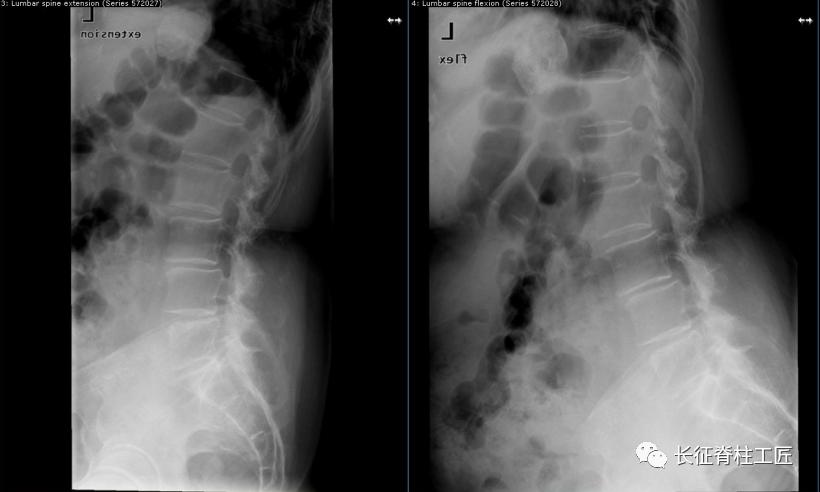

入院检查,腰部疼痛,后伸时加剧,局部压痛,双下肢肌力减退。X线检查,L4、L5骨质增生,MRI显示L4/L5、L5/S1椎间盘突出,马尾神经受压明显,被确诊为腰椎管狭窄症。